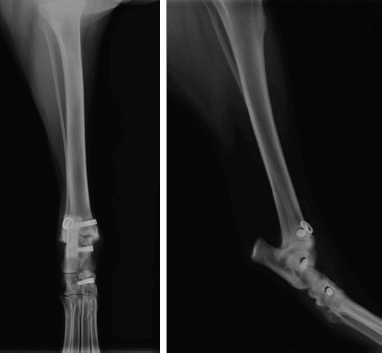

An approximation in the third drilling (distal reconstruction of the long head of the MCTL) was observed during the immediate postoperative radiographic control (Fig. 6). No other intraoperative complications occurred. Unfortunately, postoperative advice was not followed properly. The bivalve resin boot was completely removed at only 2 weeks postoperatively. However, a first radiographic check at 11 weeks showed good valgus stability of the tibiotarsal joint and the orthopedic examination showed a return to subnormal function of the pelvic limb during locomotion. At 12 months postoperatively, valgus stability of the tibiotarsal joint was maintained and the pelvic limb returned to normal function during locomotion. At 16 months post-op, radiographic control showed ovalization of the bone tunnels with no clinical impact on the stability of the tibiotarsal joint (Fig. 7).

The dog’s body condition score did not change over the 16 months of postoperative follow-up and was still estimated at 8/9 at each of the four check-ups performed during this period (Freeman et al., 2011). However, the dog still regained full function of his operated limb by synthetic reconstruction of the MCTL.

Avulsion of the long head of the left MCTL was diagnosed in a five-year-old overweight castrated male Australian Shepherd. The context was favorable to the implementation of the surgical ligament reconstruction technique previously described. Although the immediate postoperative radiographic control showed an approximation of the third drilling (distal reconstruction of the long head of the MCTL), the surgeon chose not to reopen the surgical site (Fig. 6). The reason for this choice was that sufficient tightening torque was perceived by the veterinary surgeon during the implantation of the 4x13-mm interference screw, which was compatible with satisfactory primary fixation of the UHMWPE implant according to his empirical experience. Although external restraint was maintained for only 2 weeks and the animal did not lose weight as advised, no postoperative complications were identified and one year after surgery, the animal regained normal locomotion. This synthetic MCTL reconstruction technique thus allowed a complete and durable functional and clinical recovery without the need for invasive transarticular immobilization, such as the placement of a transarticular external fixator (TEF). However, the use of a bivalve resin boot was recommended for a minimum of 6 weeks, which was not respected. In addition, the animal did not lose weight as advised. Early weight-bearing on the limb without any other form of restraint and the excess weight were potentially the cause of the progressive ovalization of the tunnels observed on the radiographic images taken 16 months postoperatively. In humans, obesity has been shown to be a leading risk factor for intraoperative complications in total hip arthroplasty (Haynes et al., 2017). Similarly, weight loss in dogs would be an essential element in the treatment of osteoarthritis, which is a frequent complication in osteoarticular surgery (Marshall et al., 2009). The ovalization of the tunnels could lead to a loss of biomechanical strength of the fixation system owing to a reduced contact surface in the bone tunnels at the bone/UHMWPE implant/interference screw interface. This loss of strength could even lead to implant slippage at this interface, resulting in a complete loss of functionality of the fixation system. However, none of this was observed from a clinical point of view during the 16 months of postoperative follow-up. The tibiotarsal joint always remained stable in valgus position. A secondary biological stabilization (Kulendra et al., 2011) may have reinforced or even supplemented the primary mechanical stabilization achieved during surgery and thus ensured durable stability of the tibiotarsal joint.

Fig. 7. Profile (left) and front (right) radiographs of dog’s left pelvic limb at 16-month postoperative check-up.